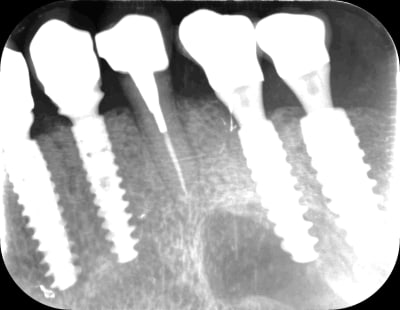

t as le la chance je viens d'avoir une urgence pour une 15 :

dérive mesiale des dents naturelles tu dis ?

Mmmmm ouaich ouaich

et donc , comment il a réussi a la visser cette couronne ( 36 ) ?

là , il y a perte de contact en distal .

et si on regarde le secteur 40 , ç est la confirmation , a mon avis , ça , ç est un pb de décalage latéral qui a cassé la ceram .

bon , bien , et si on regardais mon urgence , maintenant ?

( 15 mobile , la couronne bouge , fait mal , et fait clic clic quand on tire dessus . on lui a donné des AB il y a quelques jour )

ben voilà une belle perte de contact :-) fracture de l angle distal + mesialisation , comme de l autre coté ? a ben non pas mesialistion , pas possible

il y a des espaces de partout , alors que d apres la patiente , elle avait du mal a passer le fil en 2014 .

apres enquête , la 13 a merdé et l implant a ete reposé 7 mois plus tard .

Bref , tout ça pour dire qu avant d invoquer la fatalité mesialante galopante , il faut d abord equilibrer , et suivre les cas pour les re-equilibrer si necessaire .